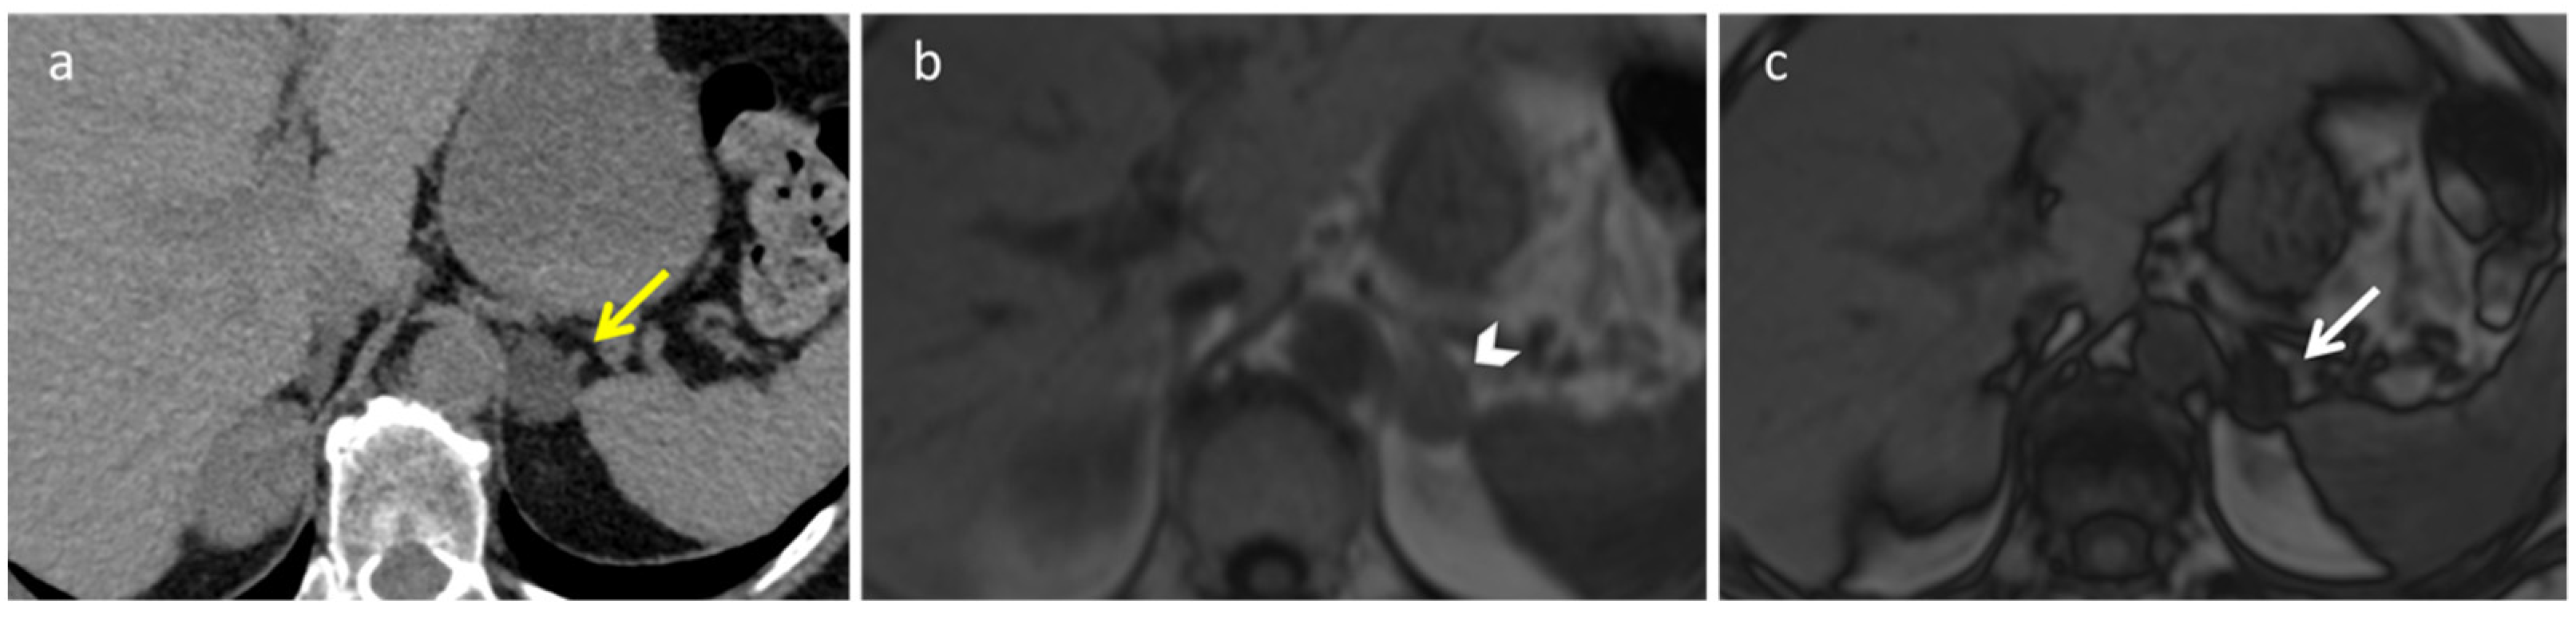

2.5. Schwannoma